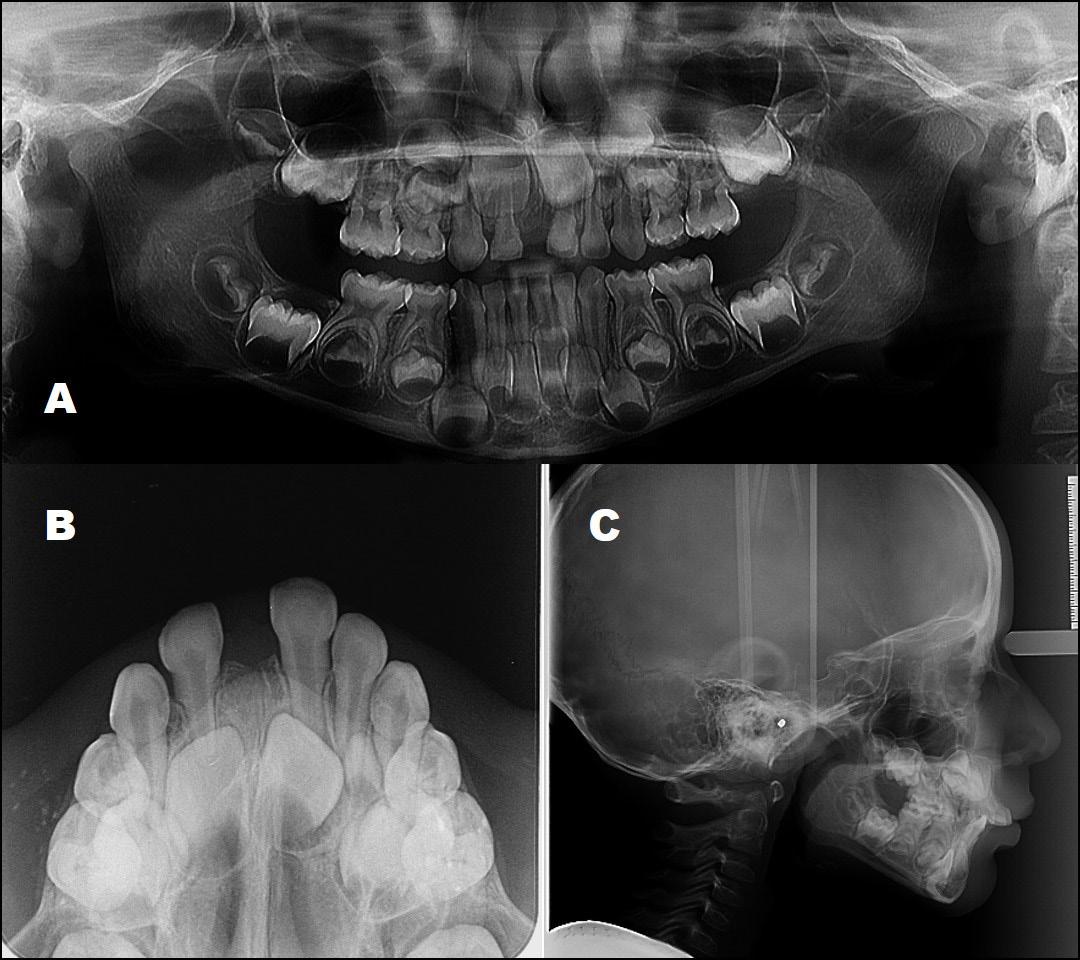

Standard orthodontic pretreatment records (T0) were obtained (Figure 1). The same operator obtained the lateral cephalogram and OPG using the same machine. The lateral cephalograms were traced manually with the standard technique by a single

investigator and a total of 06 skeletal, 11 dental, and 03 soft tissue parameters were measured. Selected patients were also subjected to Acoustic pharyngometry (AP) for a three-dimensional evaluation of the upper airway. Fixed orthodontic appliance (022” MBT PEA) was bonded on both maxillary and mandibular arch, with banding of first & second molars. A standard wire sequence was followed till the full slot engagement with SS wire (19 X 25”) was achieved. A complete set of records were made to register the beginning of the fixed functional phase (T1) (Figure 2). Forsus appliance (FFRD) was fitted for each patient, push rod hooked on the archwire between canine and 1st premolar in the maxillary arch and distal end of open coil spring connected with the ‘L’ pin to the 1st mandibular molar. Maxillary and mandibular components of the Forsus FRD were connected to provide a forward thrush to the maxilla and a backward thrust to the mandible during the closure of the mouth (Figure 3). The functional phase with Forsus FRD continued till the desired objectives were achieved i.e., achieving positive overjet as well as satisfactory improvement in soft tissue profile.

To enhance the skeletal effects of the Forsus appliance, the indirect anchorage was obtained using TADs (temporary anchorage devices), placed in the maxillary arch, distal to canine. Post-functional records were made after the removal of Forsus FRD (T2) (Figure 4). Fixed orthodontic therapy continued to settle the occlusion and patients were debonded (Figure 5).

Figure 1:Pre-treatment Orthodontic records

Figure 2: Pre-functional Orthodontic records

Figure 4: Post functional orthodontic records

Figure 5: Post-treatment Orthodontic records

Figure 3: Forsus appliance in situ